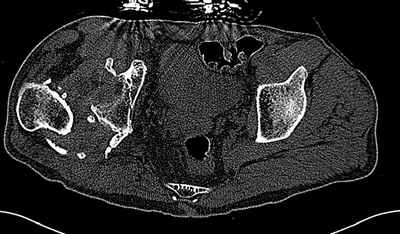

Уважаемые коллеги. Пациент 30 лет 3 года назад в результате травмы получил травматический дефект нижних конечностей до в/3 голеней, был пропущен вывих бедра.

В настоящее время очень неплохо ходит на протезах, движения в неоартрозе близки по объему к здоровой стороне. Основная жалоба - выраженная боль при ходьбе. планируем двухэтапное эндопротезирование - задним доступом мобилизовать проксимальный отдел бедра, резецировать шейку, аппаратом низвести бедро(головку оставить там где она есть, так как больших дефектов не видно(может пригодится в последующем?)). Вторым этапом бесцементное эндопротезирование. Насколько такой вариант реалистичен? Доступ для второго этапа? Может быть другие варианты?С уважением, Максим

На последнем срезе КТ задний край практически отсутсвует по сравнения со здоровой стороной. Разумеется, что это плоскостное изображение, но головка вывихнулась не только в плоскостную щель захваченную на КТ. Если вы считаете, что удастся установить туда чашку даже низкопрофильную, остается пожелать вам успехов. Но перед этим можно смоделировать установку чашки на скиаграммах КТ.

За пожелание успехов - спасибо, думаю это пригодится, не очень понял про плоскостную щель, специально предоставил срезы на уровне свода - он цел, дефект заднего края ниже, за счет заглубления он будет еще меньше, по данным 3d - должно получиться.